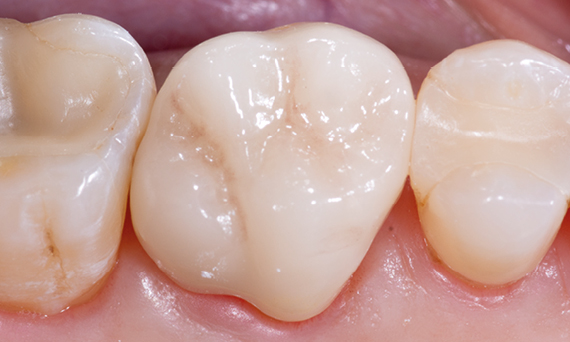

After

Chairside-fabricated restoration made from an advanced lithium disilicate ceramic, CEREC Tessera.